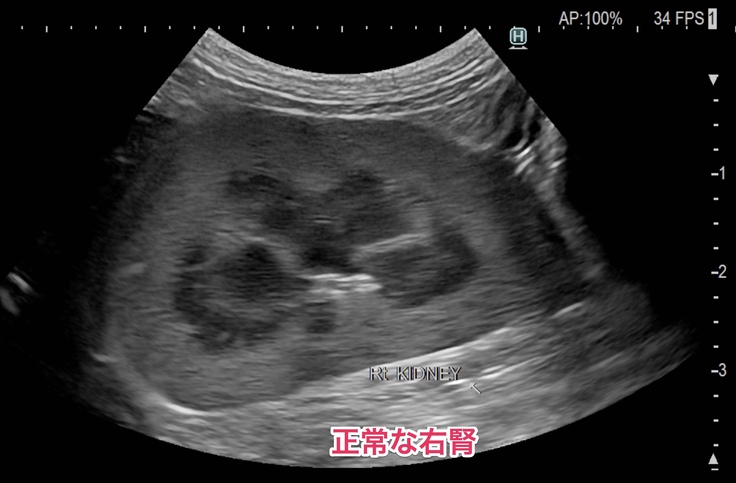

●左側の腎臓と腎盂が肥大して、ほとんど機能していない状態。(右側の腎臓と腎盂は正常)